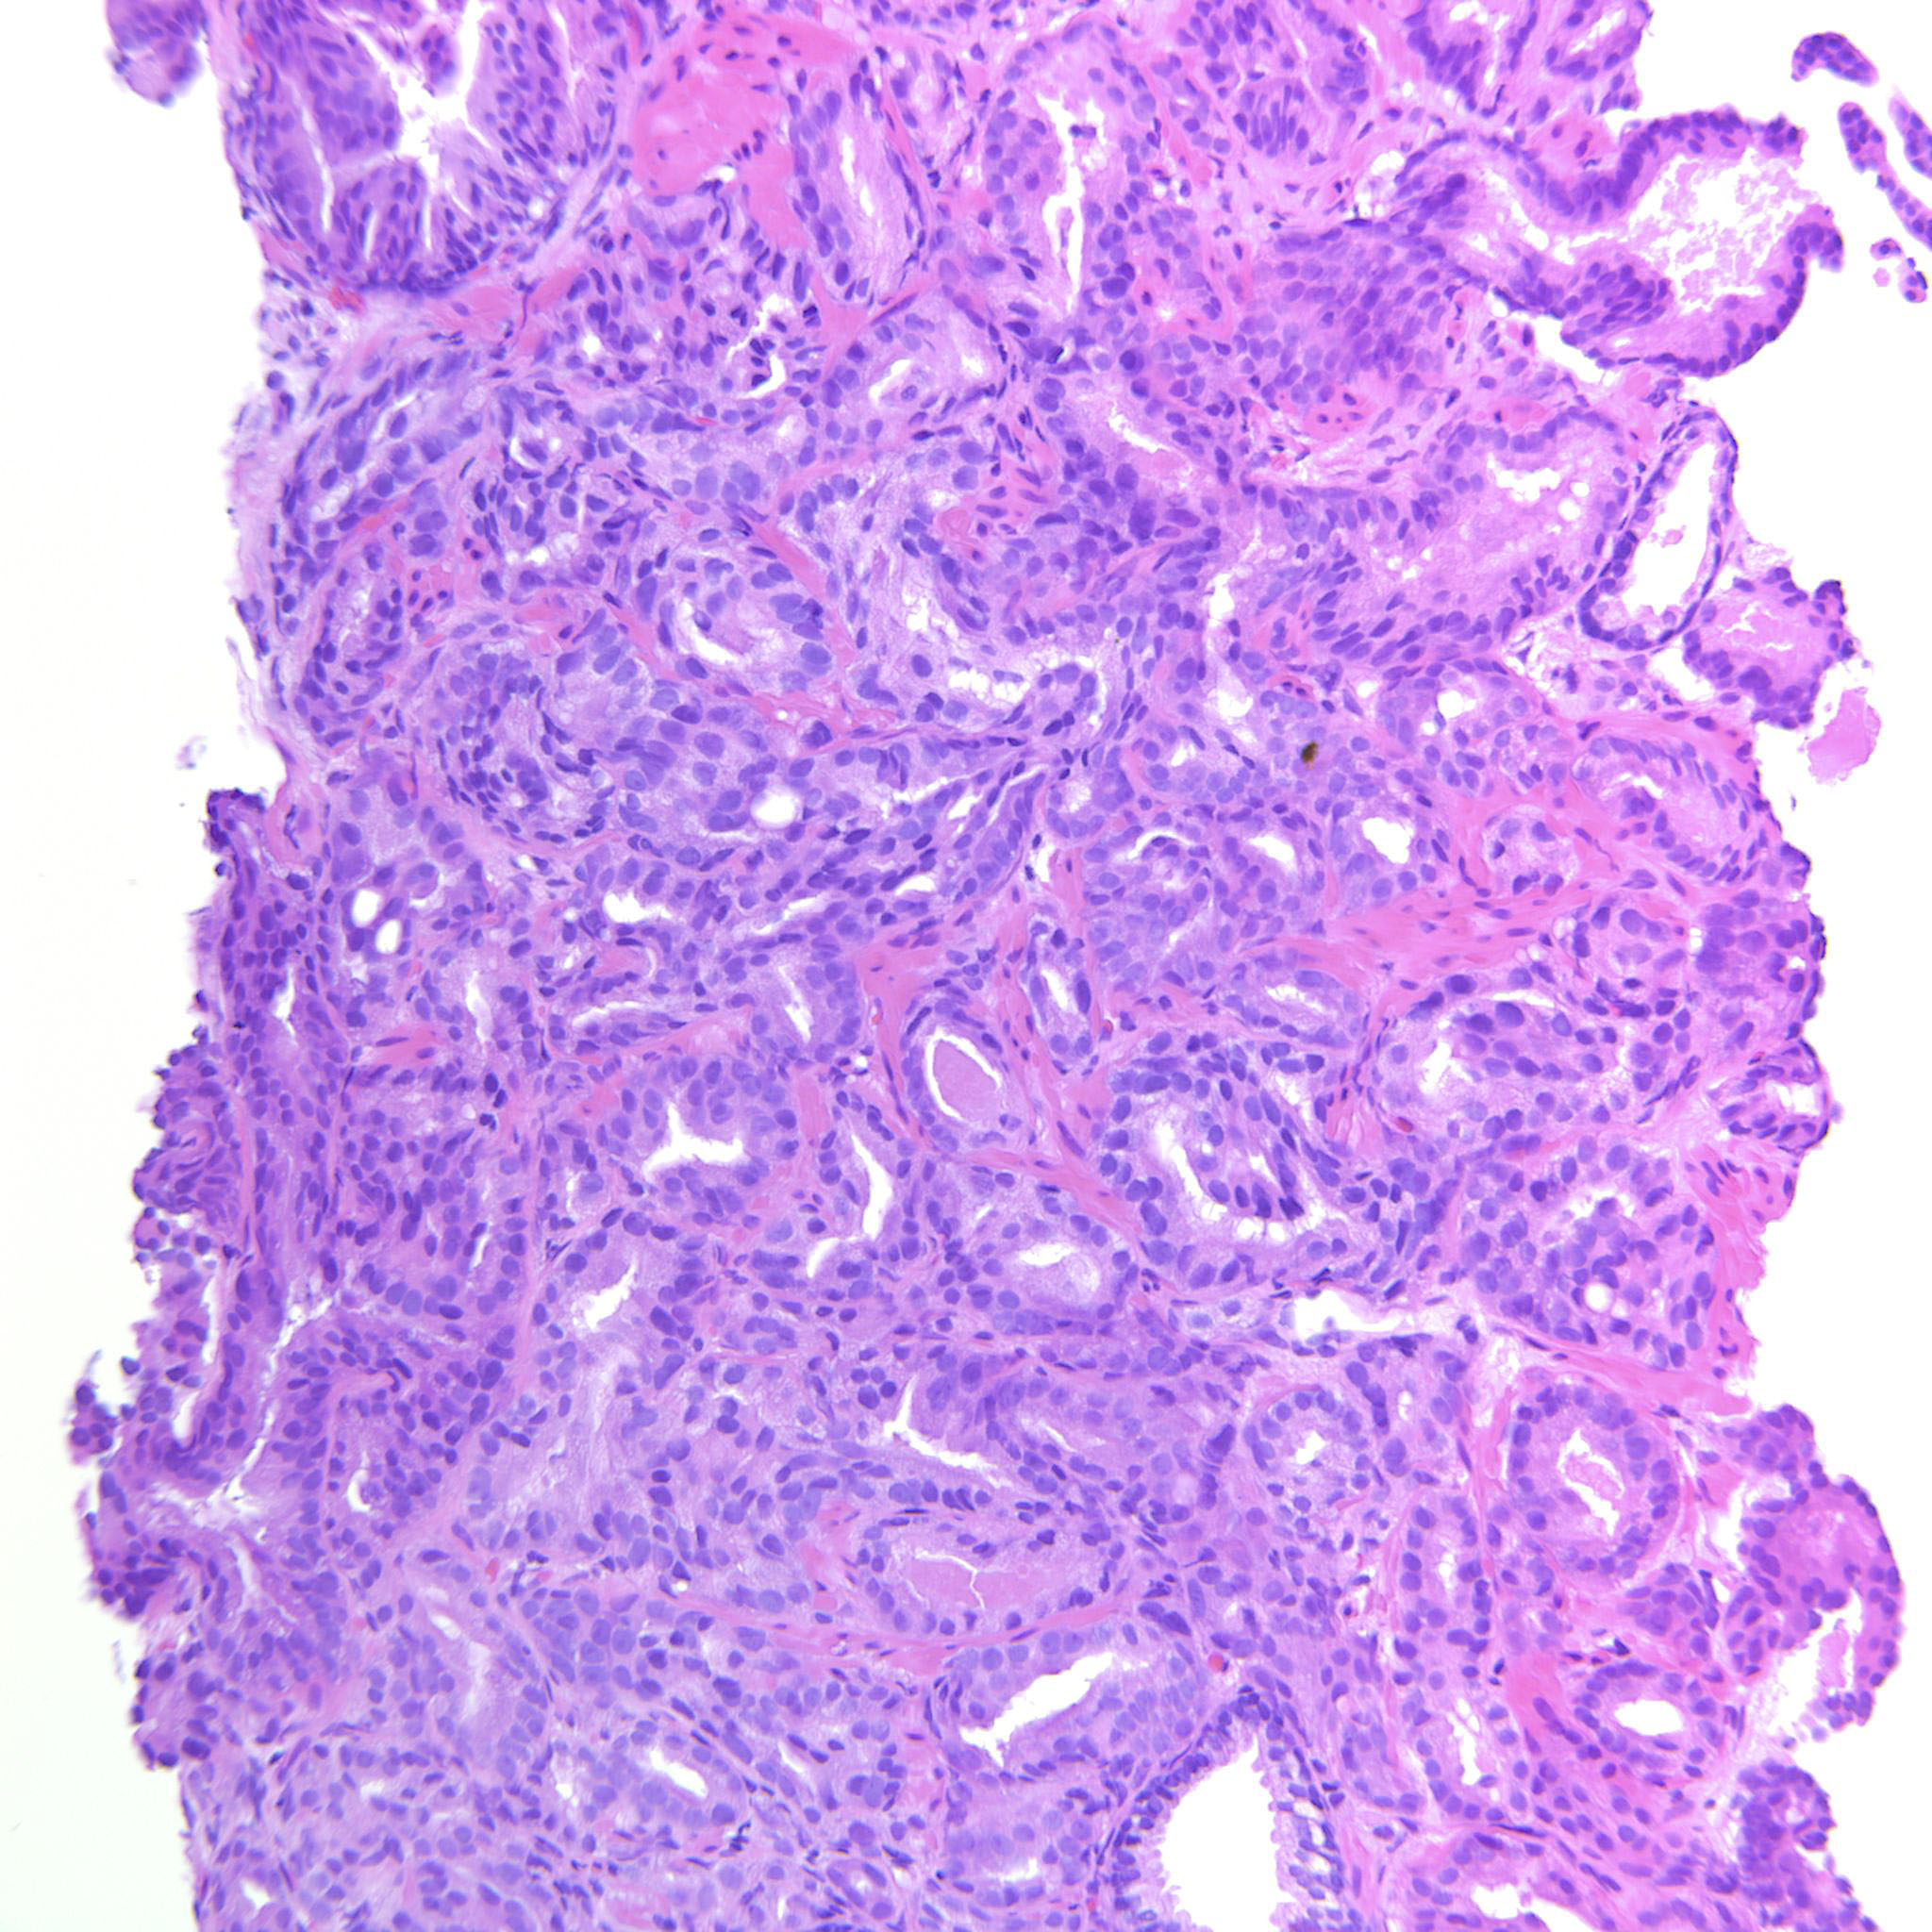

Prostate cancer grading

Case ID: 537